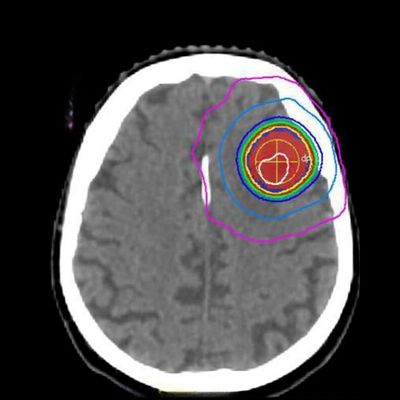

Beynin damarsal hastalıkları olan AVM (Arteriovenöz Malformasyon) ve kavernomlarda Gamma Knife'dan yararlanılabilir. Özellikle cerrahisi riskli, boyutu da 3 cm'yi geçmeyen AVM'lerde Gamma Knife düşünülebilir.

Gamma Knife'ın sık kullanıldığı alanlardan biri beyin metastazlarıdır. Bunlar kötü huylu tümörlerdir. Etkililiği sınırlı olmakla birlikte beynin kendisinden köken alan malign tümörlere de uygulanabilir.

Beynin kendi dokularından köken alan menenjiom ve vestibüler schwannoma gibi çoğu zaman da iyi huylu olan tümörler Gamma Knife'ın en sık kullandığı ve olumlu yanıt verebildiği beyin tümörü tipleridir.